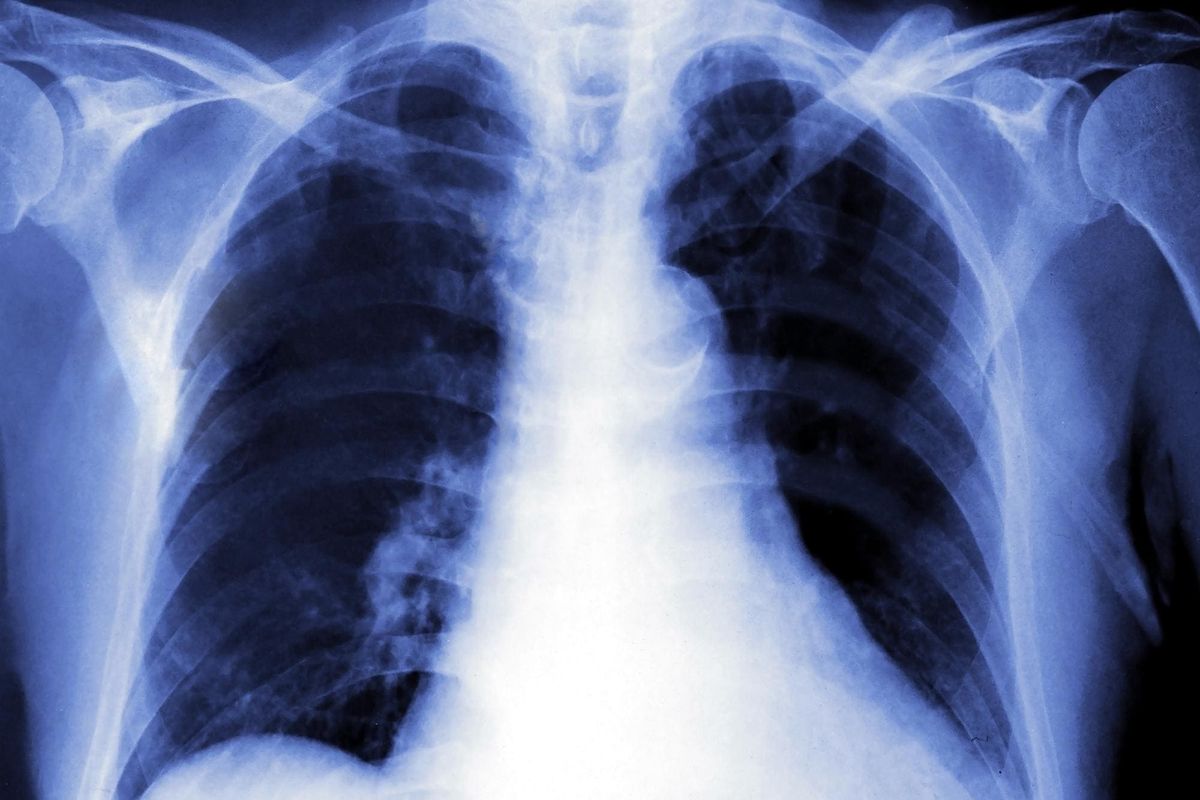

Одним из самых распространенных сегодня заболеваний является туберкулез. Он имеет инфекционную этиологию и вызывается несколькими видами патогенных микроорганизмов, которые передаются воздушно-капельным путем. Стоит сказать, что палочка Коха, которая является возбудителем недуга, не поддается воздействию окружающей среды, поэтому такие бактерии способны продолжительное время находиться в почве и воде. Такая устойчивость микроорганизмов объясняет широкое распространение недуга по всему миру. Своевременное диагностирование заболевания сокращает риск развития серьезных последствий, поэтому так важно знать, как проявляется туберкулез, его симптомы и первые признаки. Лечение необходимо начинать только после консультации врача.

По мнению медиков, это заболевание достаточно сложно диагностируется. Первые признаки туберкулеза во многом зависят от его стадии, формы и индивидуальных особенностей организма инфицированного человека. В большинстве случаев этот недуг поражает легочную ткань, но имеют место случаи инфицирования других органов и систем. К самым распространенным разновидностям туберкулеза, которые характеризуются особой симптоматикой, относятся такие:

Согласно статистике, ВОЗ от туберкулеза ежегодно умирают около 2 миллионов человек. В России это заболевание уносит примерно 25 000 жизней каждый год. Потому не следует относиться к первым признакам туберкулеза пренебрежительно. Вовремя выявить заболевание позволит профилактическая флюорография, которую следует проходить как минимум раз в 2 года.